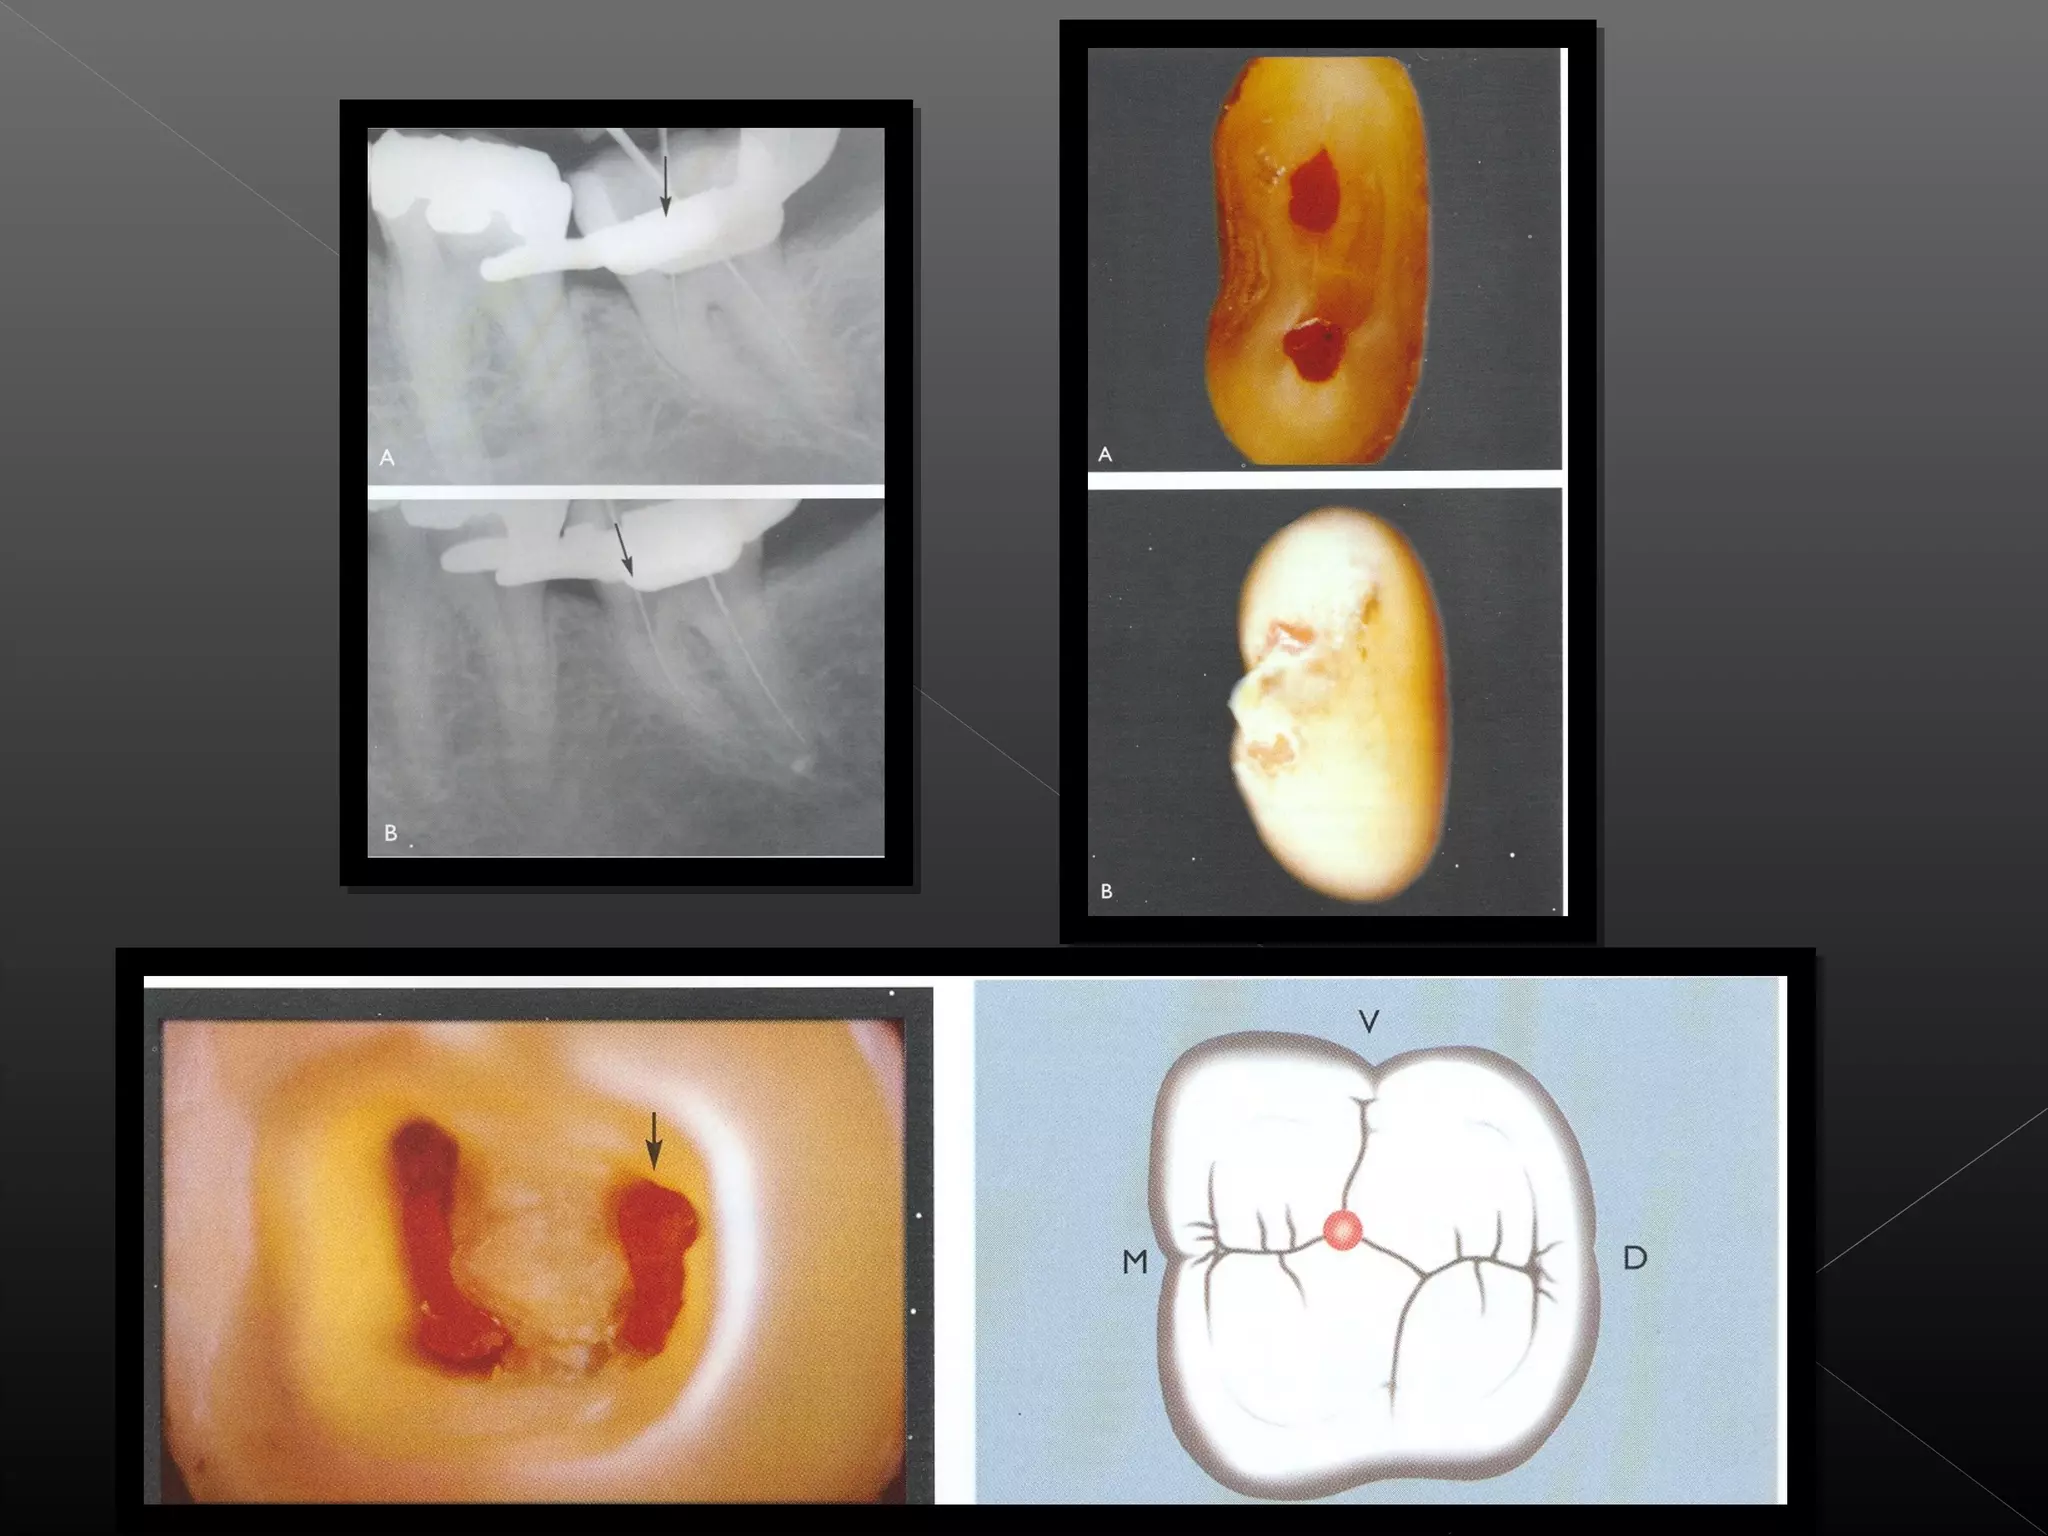

El documento describe los pasos y herramientas utilizadas en el diseño y preparación de una cavidad dental, incluyendo la selección del punto inicial de penetración, la forma y dirección de apertura, la eliminación de caries y restauraciones existentes, y la limpieza de la cavidad utilizando herramientas como exploradores, fresas de bola de diferentes tamaños, cucharillas y fresas endodónticas.